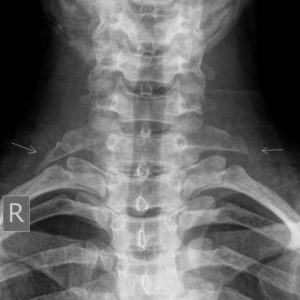

Xương sườn cổ 7

Lượt xem: 3243» 29-10-2018 -